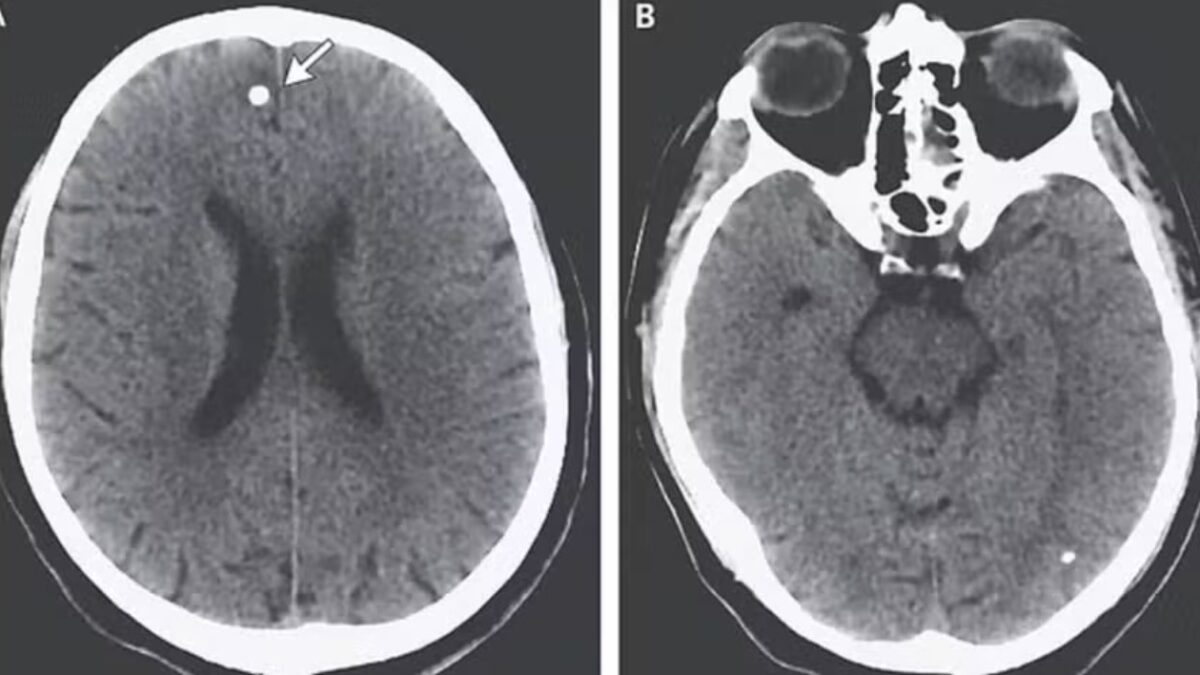

Ovos de tênia no cérebro de paciente nos EUA (Foto: Reprodução)

Essa ingestão, porém, pode levar à liberação de ovos do parasita na corrente sanguínea, que podem circular até alcançar o cérebro e causar sintomas como convulsões potencialmente fatais. Os médicos apresentaram nas redes o caso de uma mulher de 21 anos, que eles chamaram de “TE”, para fazer um alerta. Segundo os especialistas, ela comprou uma caixa de pílulas contendo ovos de tênia online.

Os médicos, agora examinando seu cérebro mais de perto, encontraram diversas lesões preocupantes no órgão. Após questionamentos persistentes sobre sua dieta e hábitos, “TE” confessou aos médicos que consumia ovos de tênia que havia comprado online. A análise do que exatamente ela havia comprado revelou a presença de tênias pertencentes a duas espécies diferentes de parasitas.

Mas, os problemas no cérebro foram causados pelos ovos da outra espécie, chamada de Taenia solium. Ela é comumente encontrada na carne de porco e libera pequenos ovos que, quando entram na corrente sanguínea, como foi o caso de “TE”, se espalham para tecidos como músculos e cérebro levando a uma doença chamada de cisticercose.

Embora esses ovos não consigam eclodir fora do intestino, eles formam nódulos duros, semelhantes a cistos, que parecem caroços sob a pele. Hsu acrescentou ainda que há casos de alterações na visão, mudanças de personalidade e diminuição da função cognitiva devido a pressão exercida pelos nódulos e pelo inchaço do local, a depender do local em que se alojam no tecido do cérebro.